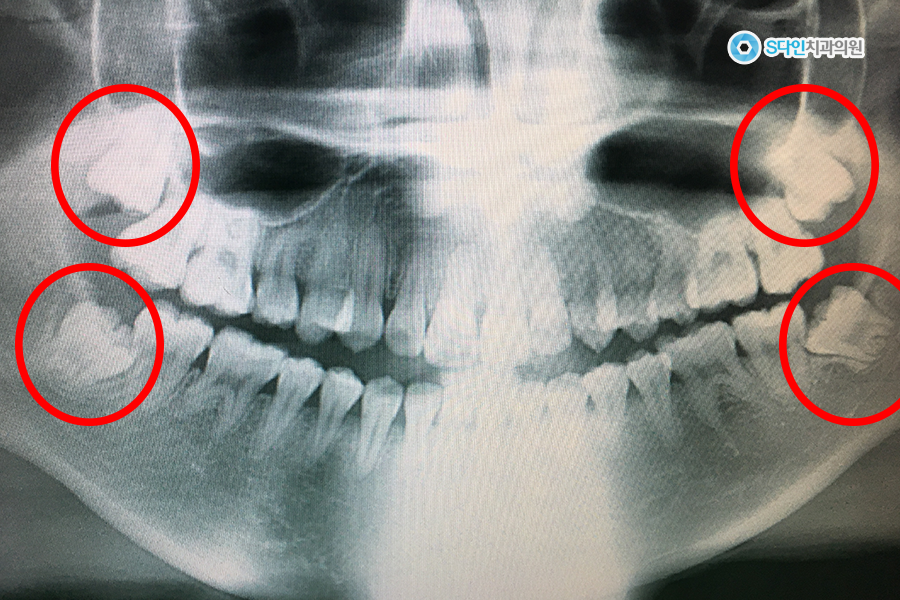

1.png 안타깝게도 네개 모두 나고 있는 모습

사랑니는 영구치가 모두 난 뒤에 맹출되는 치아이기 때문에, 날 때쯤 공간 부족에 시달립니다. 특히, 현대인은 딱딱한 것을 많이 섭취하지 않아 턱이 좁아진 상태인데요. 좁아진 턱 사이에서 잇몸을 비집고 나오다 보면 누워서 나거나 치아의 일부만 잇몸 위로 나옵니다.

그럼 바로 옆에 있는 어금니와 틈이 생기고, 그 부분에 주기적으로 음식물이 끼게 되죠. 음식물이 자주 끼는 곳은 그대로 뒀을 때 충치가 생길 확률이 아주 높기 때문에 사랑니를 미리 뽑아주시는 것이 좋아요.

사랑니는 인류가 진화하면서 퇴화한 치아로 사실상 아무 기능이 없다고 봐도 무방합니다. 하지만 어금니는 음식을 씹는데 아주 중요한 역할을 하죠. 게다가 한 번 어금니가 썩으면 치아는 회복되지 않으니, 가장 중요한 어금니를 지키기 위해서라도 잘못 난 사랑니는 발치해주시는 것이 맞습니다.